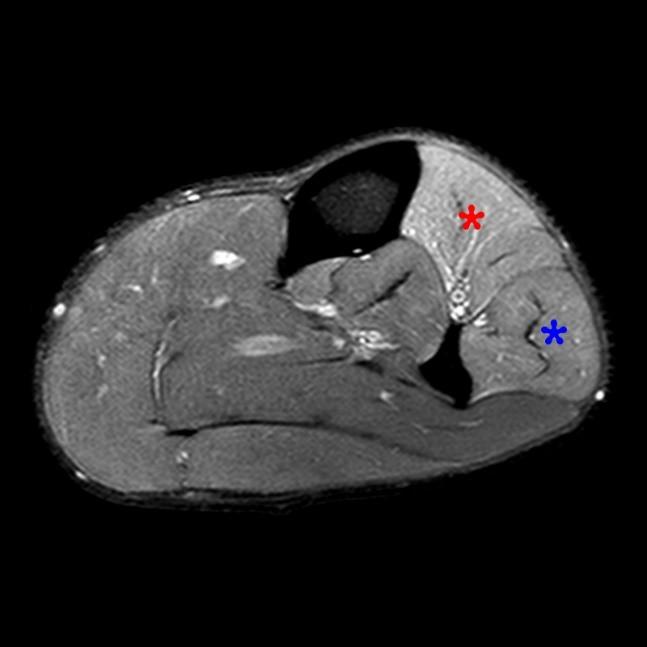

From radsource.us

Compartment Syndrome of the Leg Radsource Leg Pain Compartment Syndrome Compartment syndrome is a surgical emergency characterised by increased pressure within a closed space. Compartment syndrome is an increase in pressure inside a muscle, which restricts blood flow and causes pain. It is usually encountered in limb injuries. Leg compartment syndrome is a devastating lower extremity condition where the osseofascial compartment pressure rises to a level that decreases perfusion to. Leg Pain Compartment Syndrome.

Compartment Syndrome of the Leg Radsource Leg Pain Compartment Syndrome It is usually encountered in limb injuries. If it happens suddenly, it can be. The legs, arms, forearms, thighs, feet, gluteal region, hands, and abdomen are most prone to developing compartment syndrome. Late findings of acs can lead to limb amputation, contractures,. Leg compartment syndrome is a devastating lower extremity condition where the osseofascial compartment pressure rises to a level. Leg Pain Compartment Syndrome.